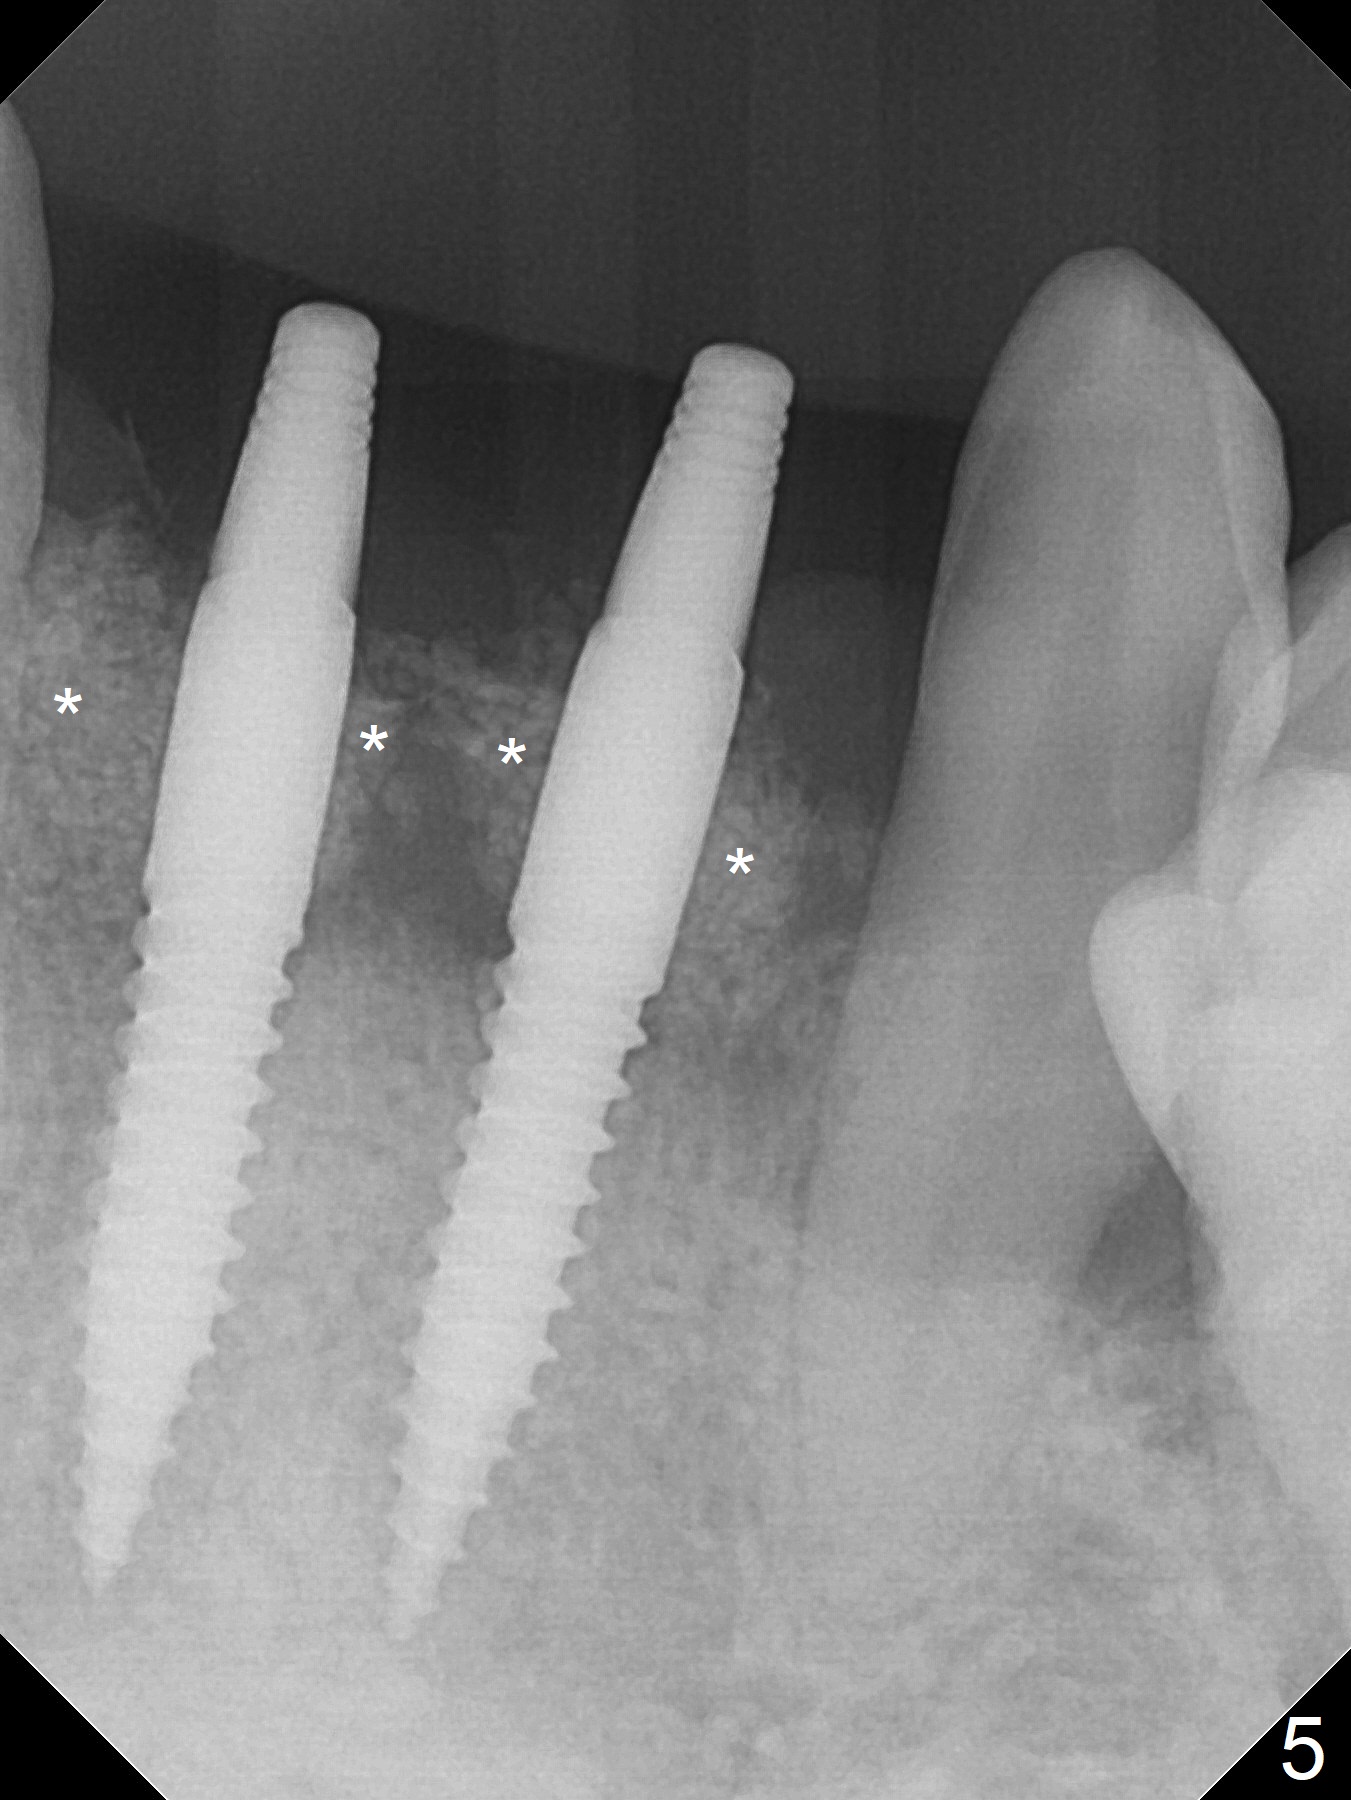

After extraction of 4 of the lower incisors, there are basically 2 sockets (#23/24 and 25/26), separated by the apparently midline bone (Fig.1 red line).  In spite of using Lindamann bur to move the 25/26 osteotomy mesially, a 3x14(2) mm dummy implant remains close to the tooth #27 (Fig.2).  The terminal branch of the Incisive Canal (<) is located between the lateral and central incisors.  A de novo osteotomy (Fig.3 (1.5 mm drill)) is made mesial to the original one (O).  While the 3x14(2) mm dummy implant is incompletely placed at #25/26, a 3x14(4) mm 1-piece one is placed at #23/24 (Fig.4).  Finally the same implant is placed at #25/26 with placement of mineralized cortical/cancellous bone (Fig.5 *).  When the large sockets are sutured, the supraerupted teeth #7-9 touch the lower gingiva (Fig.6).  The incisal edge is reduced for clearance (Fig.7).  Periodontal dressing is less likely to be dislodged with the incisal edge reduction (Fig.8,9).  A provisional FPD is fabricated 1 week postop.  Hard (Fig.10) and soft (Fig.11,12) tissues heal 5.5 months postop.  The patient returns for crown cementation 3 months post impression (9 months postop, Fig.13,14).